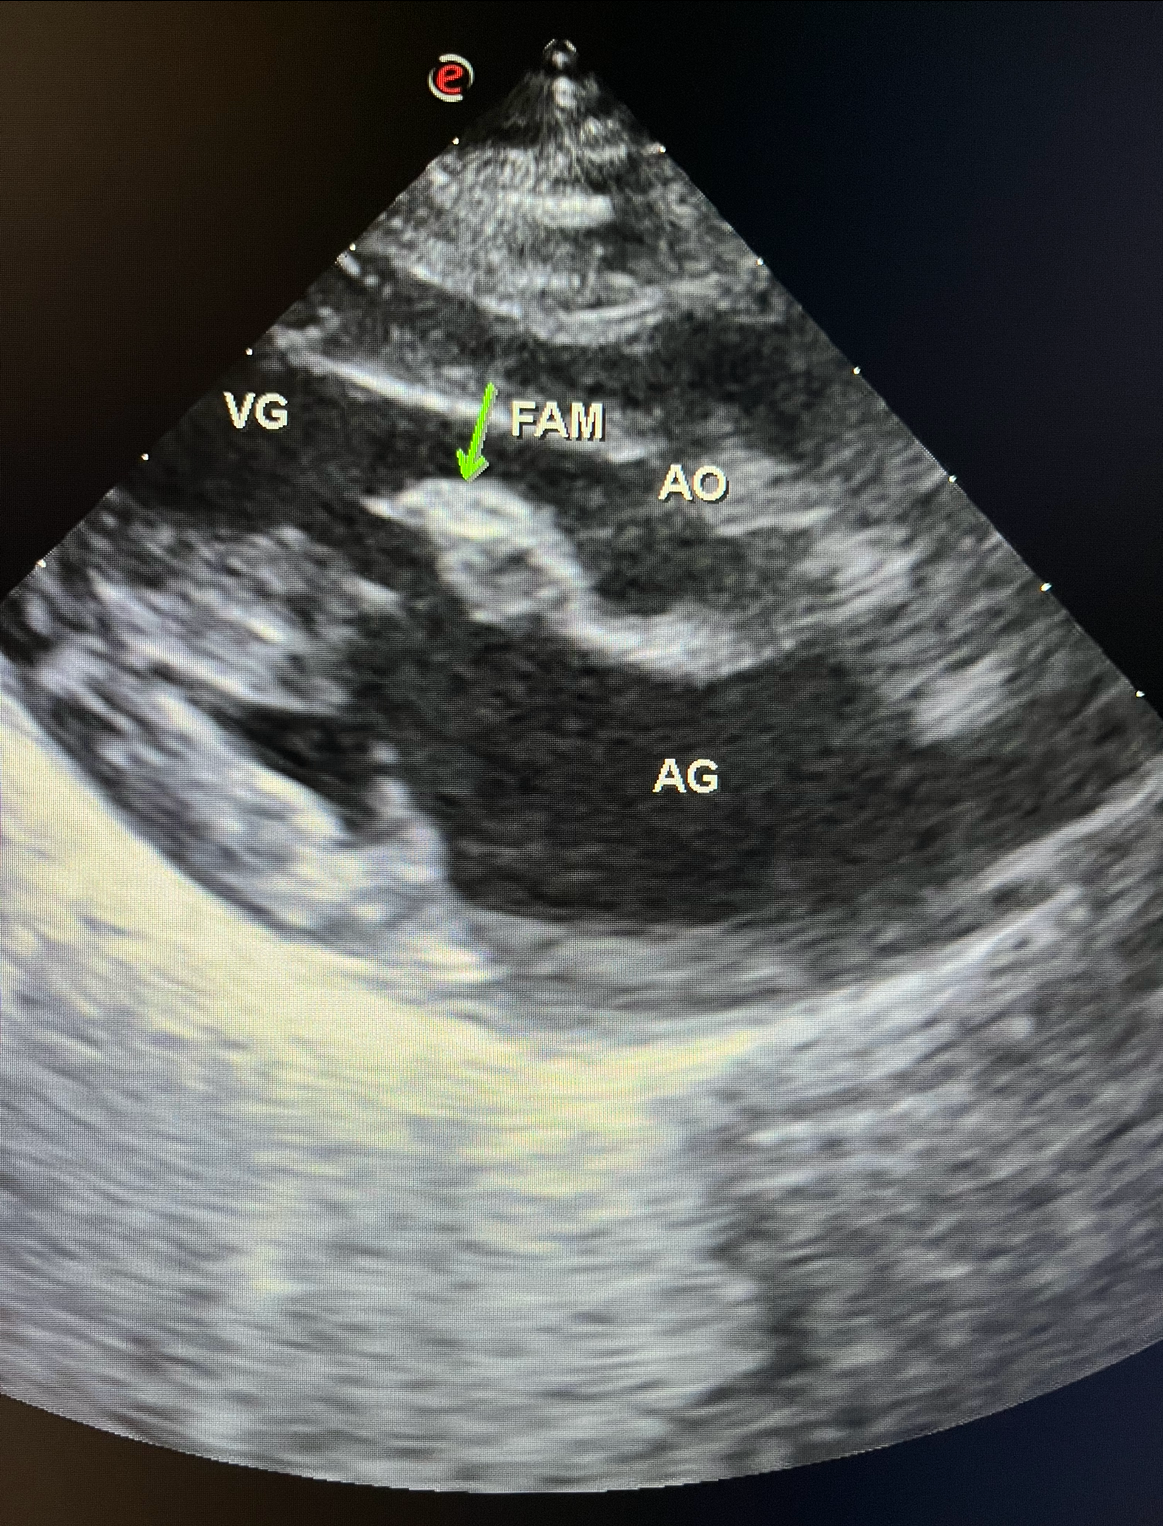

Échographie Cardiaque

Les échographies thoraciques permettent quand à elle d’étudier et de suivre l’évolution des pathologies cardiaques mais également d’observer des épanchements ou des tumeurs thoraciques.